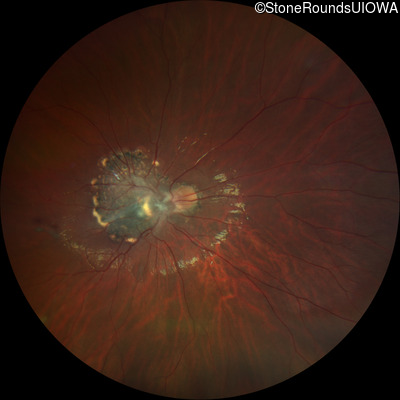

This 9 year old male was noted to have some crossing of his eyes at 2 months of age and the eye exam which followed identified a retinal lesion in the right eye. When he was six years old an epiretinal membrane was noted in his left eye. Two years later it was decided that it was a thin hamartoma in that eye as well. He underwent neuroimaging at age 7 which identified bilateral acoustic neuromas.